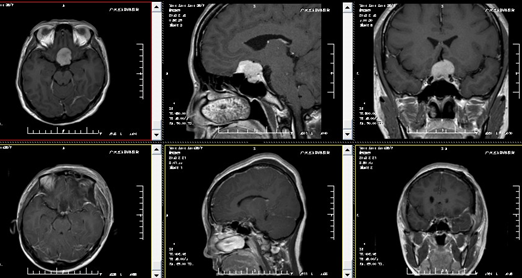

入院后完善相关检查及术前准备。由林涛主任在全麻下行手术室在全麻下行“鞍区占位性病变切除术”,手术顺利,复查头颅CT、MRI示:呈术后改变,未见肿瘤增强信号。术后病理结果回报:脑膜瘤。

以下影像图片,上排为术前,下排为术后